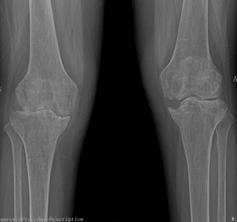

2015年10月,我院骨科二區(qū)迎來(lái)了62歲的李姓患者,她是一名類風(fēng)濕性關(guān)節(jié)炎的患者,病程10年。10年前,她被查出患有嚴(yán)重的類風(fēng)濕性關(guān)節(jié)炎,全身多處小關(guān)節(jié)疼痛,自那以后,患者就長(zhǎng)期依靠激素來(lái)控制病情。2年前,患者雙側(cè)膝關(guān)節(jié)開(kāi)始出現(xiàn)疼痛、腫脹,起初還能下地走200米左右,后來(lái)走50米都感覺(jué)費(fèi)力,雙下肢膝關(guān)節(jié)出現(xiàn)變形,靠鎮(zhèn)痛藥物才能入睡。起初患者認(rèn)為,類風(fēng)濕關(guān)節(jié)炎是自己的老病,沒(méi)得治,拒絕來(lái)醫(yī)院就診。最后,實(shí)在痛苦難忍,遂在家人的陪伴下來(lái)到我院骨科二區(qū)就診。

來(lái)院后,骨科二區(qū)唐雄主任、廖浩主治醫(yī)師熱情接待了她。經(jīng)查,患者為嚴(yán)重的類風(fēng)濕性關(guān)節(jié)炎導(dǎo)致的雙膝關(guān)節(jié)破壞,雙膝關(guān)節(jié)內(nèi)翻畸形并嚴(yán)重的骨質(zhì)缺損,同時(shí)由于患者長(zhǎng)期服用激素類藥物,其全身骨質(zhì)均有嚴(yán)重的骨質(zhì)疏松?;颊叩弥∏閲?yán)重性后,感到失望、沮喪,唐雄主任信心滿滿地安慰道,“您這種情況行膝關(guān)節(jié)置換術(shù),就能徹底解決關(guān)節(jié)疼痛和雙膝關(guān)節(jié)不能活動(dòng)的問(wèn)題?!庇谑牵∪擞种匦氯计鹆藢?duì)生活的希望,并要求盡快進(jìn)行手術(shù)治療。